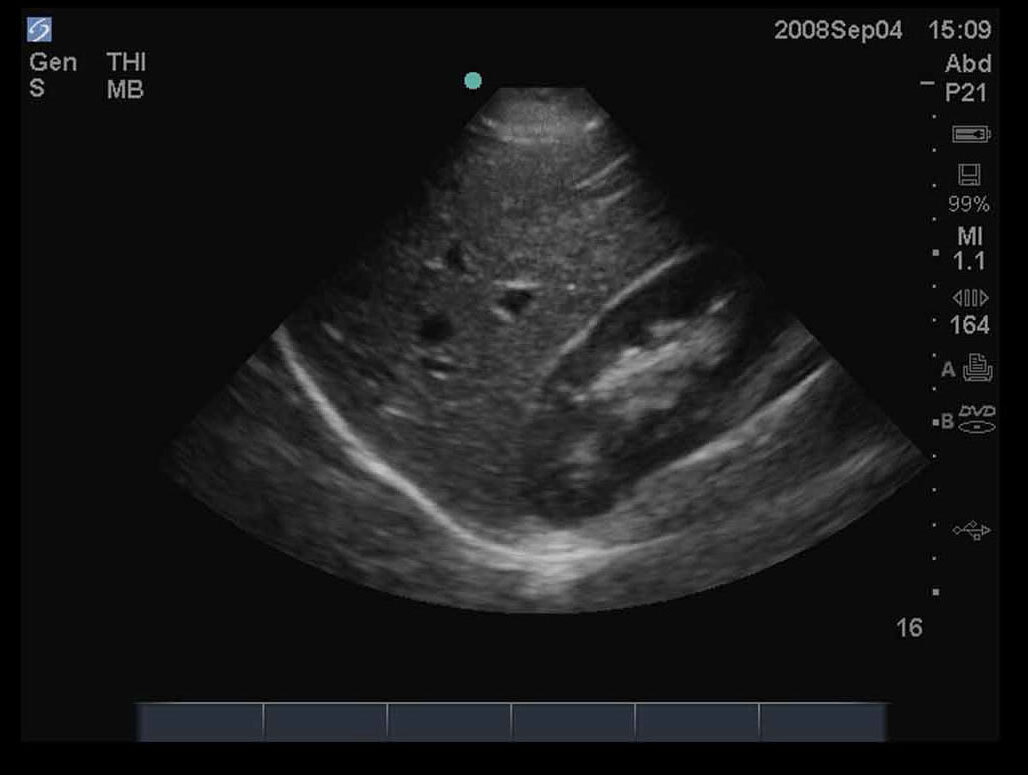

FAST 右上四半部 (RUQ) 2 画像

M-Turbo